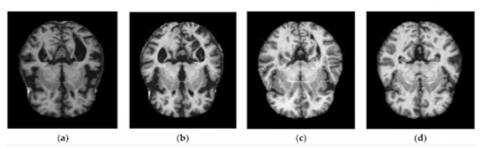

In this research, the dataset was obtained from various websites with each and every label verified. This dataset is available on Kaggle [18] and comprises 6,400 images depicting four phases of Alzheimer's disease: mild dementia (MD), moderate dementia (Mod. D), non-demented (ND), and very mild dementia (VMD). Importantly, it's worth noting that each of these phases of Alzheimer's disease in the dataset is based on different individuals. The distribution of MRI pictures for each class, as well as the number of images in the training and testing sets, are shown in Table 1. The MD class is composed of 896 images, while the Mod. D class consists of 64 images. In total, the ND class comprises 3,200 photos. Lastly, the VMD class encompasses 2,249 images. The examples of the images have been shown in Figure 3.

Figure 3. Alzheimer MRI dataset: (a) MD, (b) Mod.D, (c) ND, and (d) VMD